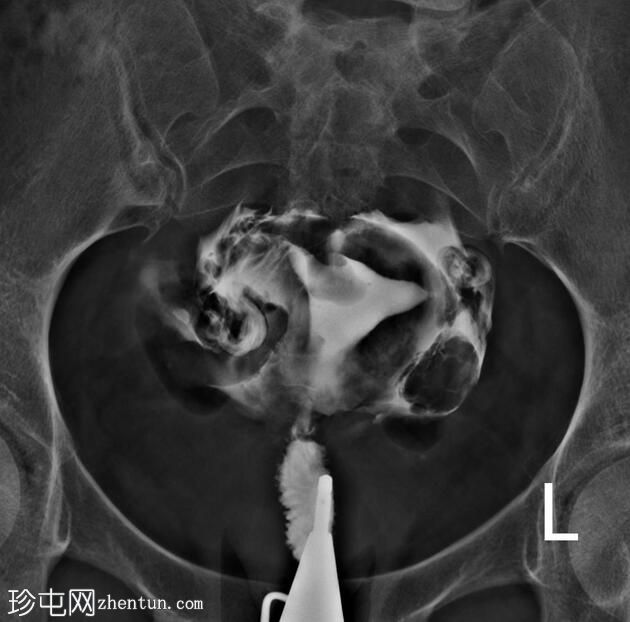

X线片

正位片

子宫内膜腔内可见一卵圆形充盈缺损,边缘光滑,强烈提示子宫内膜息肉的存在,生理盐水灌注子宫声学造影(未显示)证实了这一诊断。

鉴别诊断中还应考虑黏膜下肌瘤。